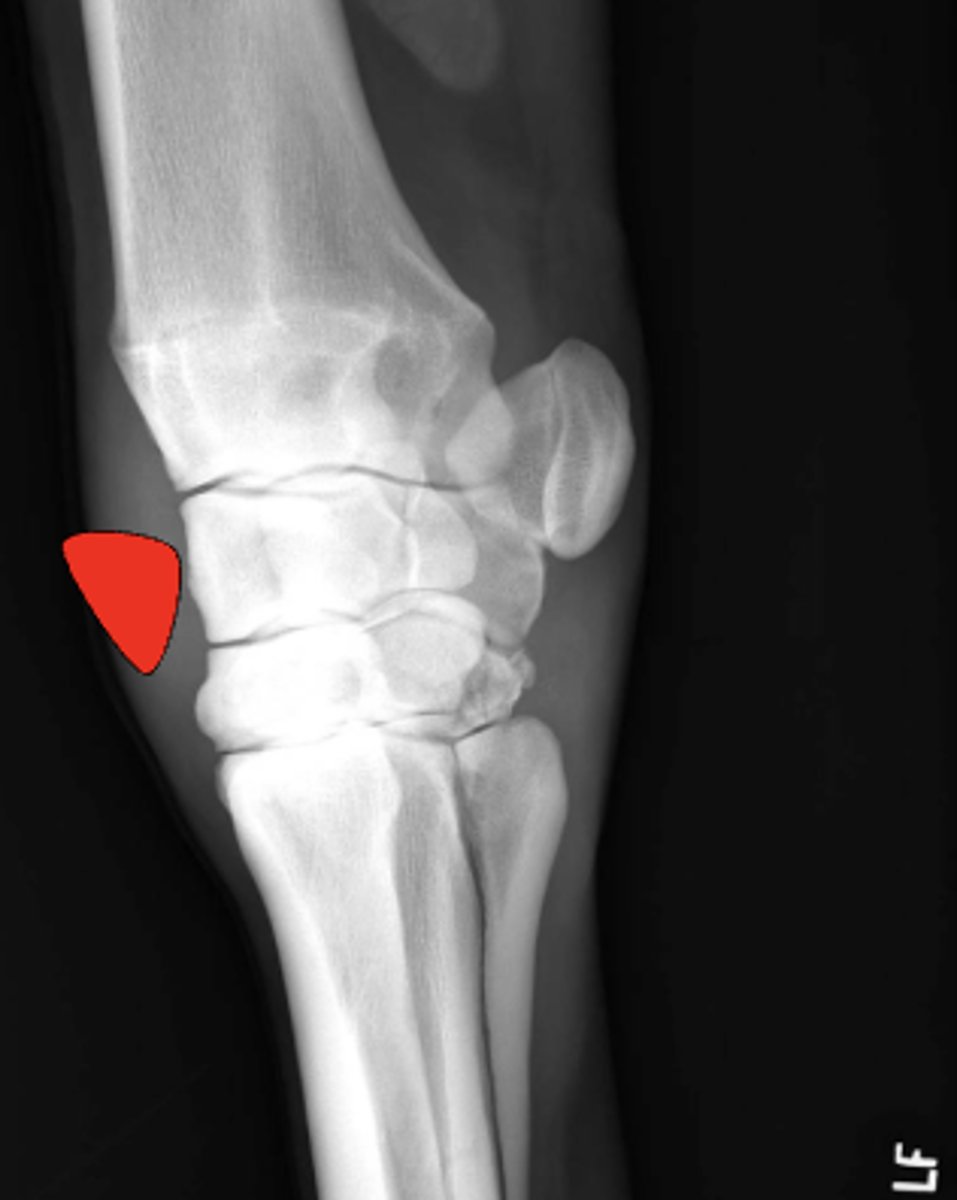

Dorsomedial

Where is this fragment located?

Type IV

Which Salter-Harris fracture is pictured?